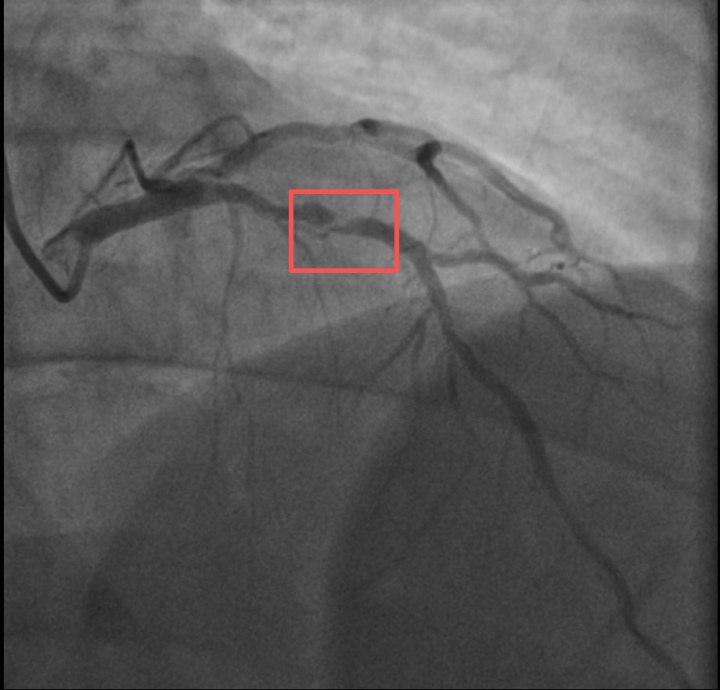

介入治疗前影像图

孙先生花了一年时间

体重从原来的96KG瘦到90KG

但让他没想到的是

意外还是来了

近日,他带孩子去练习羽毛球,没想到亲自上场挥杆仅10分钟左右,孙先生就因心前区剧烈绞痛被送进了急诊。

浙江医院心血管内科的医生分析,剧烈运动导致这位患者心脏的不稳定斑块破裂,进而造成前降支近段次全闭塞。所幸送医及时,孙先生的身体险情被化解。